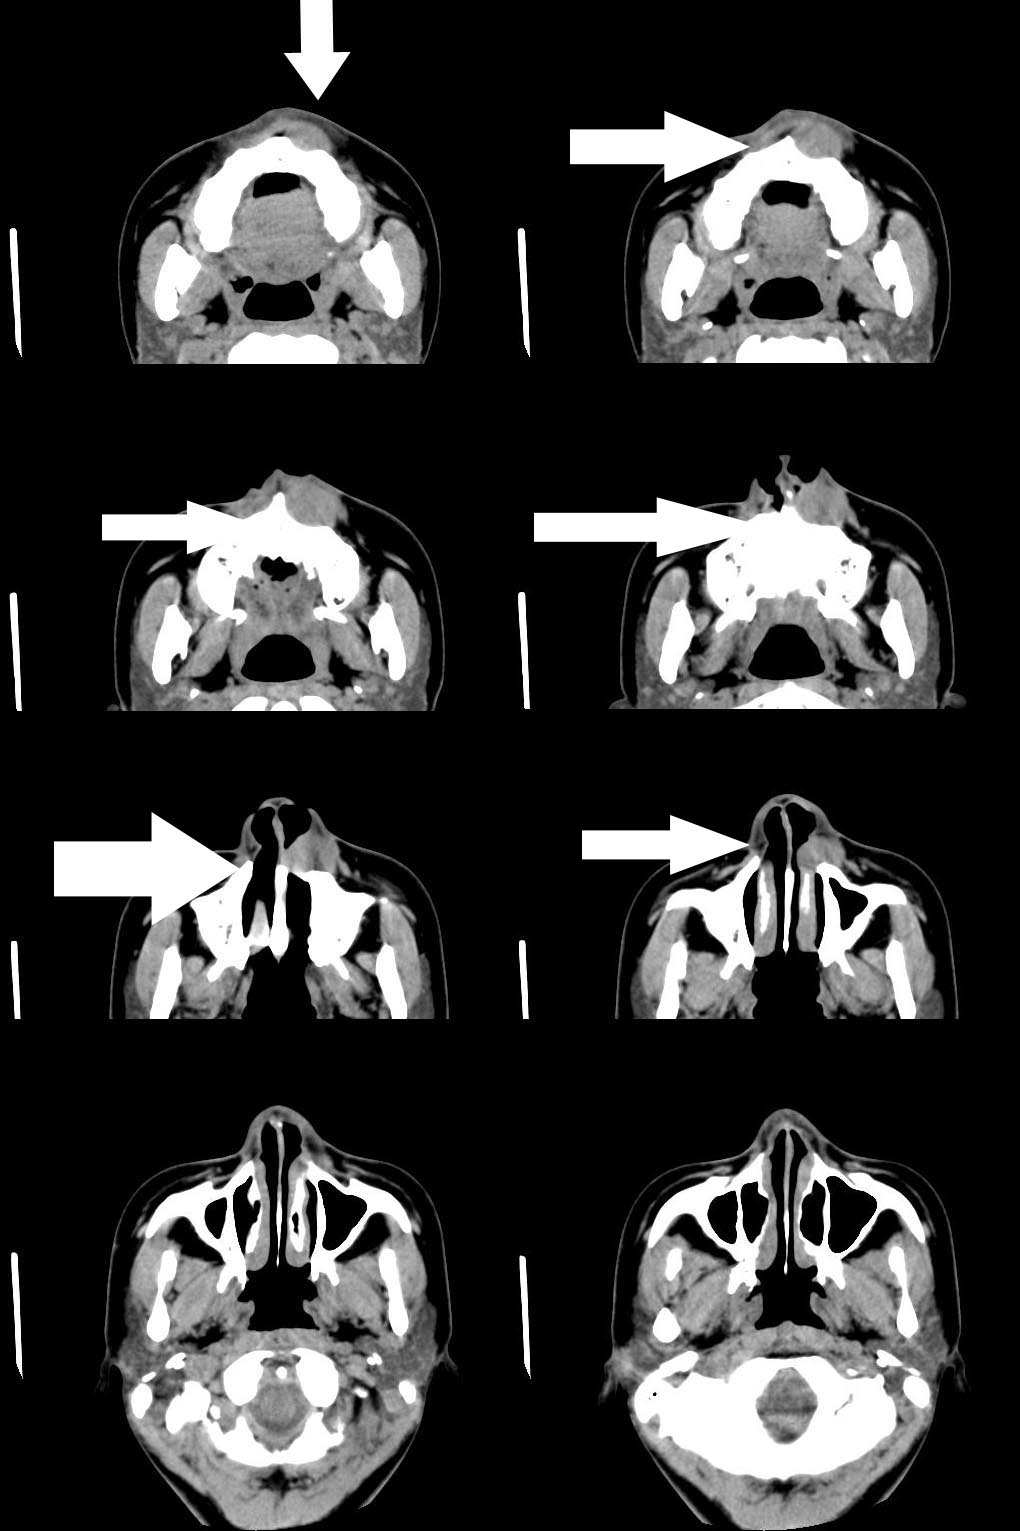

标题: CT7523:[分享]考虑鼻前庭囊肿!

病人诉近20天左鼻侧隆起肿胀

支持楼主意见,局部骨质有吸收.